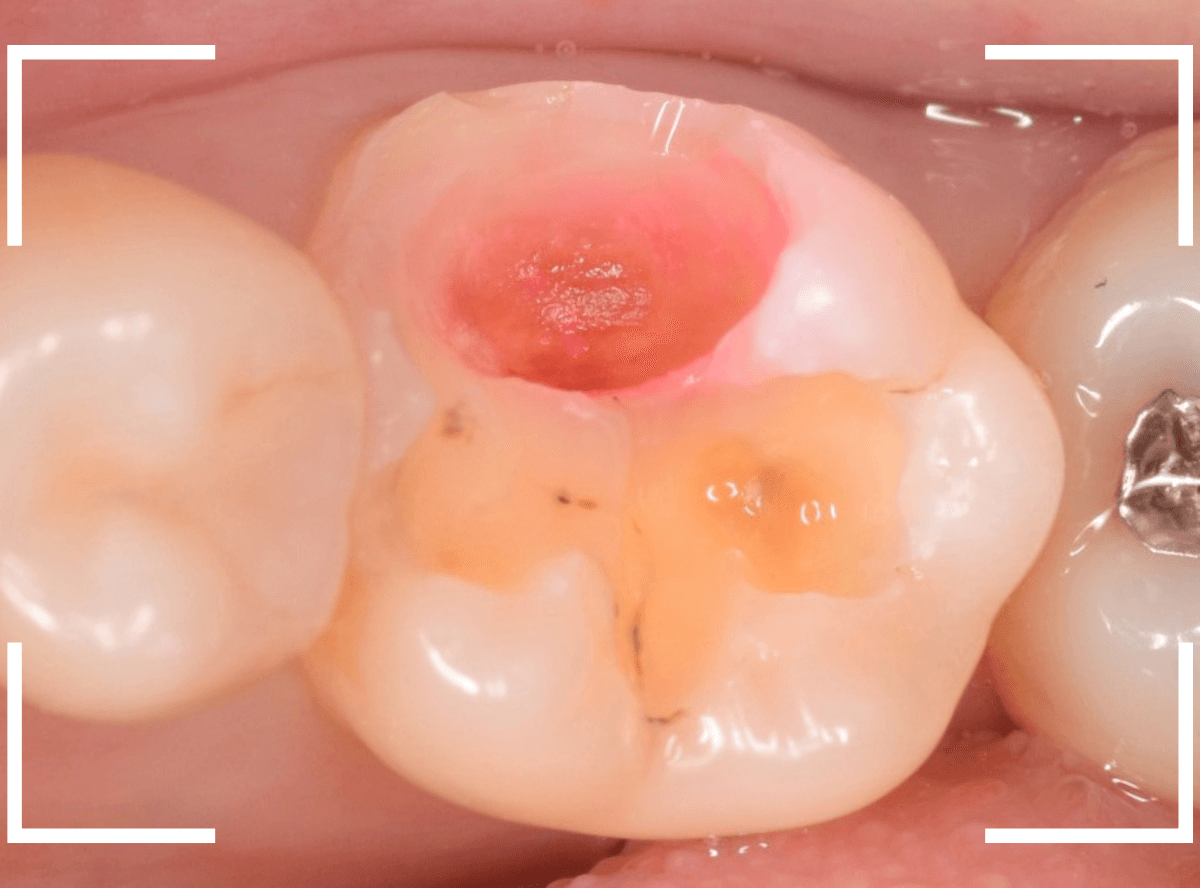

Case.15 歯の側面のレジンの中のわかりづらい虫歯

検診で、金属のつめ物のの中と、歯の側面に虫歯が見つかった方です。

まずは、手前(左)側の治療です。

こちらが、お口の中を見たところです。

〇部の中に虫歯があると思われます。

今回のように、金属のつめ物やレジン治療をしてある歯の側面の虫歯の診断はわかりづらく、難しいです。

金属のつめ物を外したところです。

この白いセメントの中に虫歯があると思われます。

セメントを除去したところです。

赤く染まっている部分が虫歯です。

真っ赤ですね(^^;)

まだ薄く染まっています。

もう少し除去する必要があります。

全ての虫歯が取れました、かなり深い神経まで近い虫歯でした。

金属のつめものをを外します。

つめものの下で虫歯になっていたせいで、虫歯と一緒に手前側のエナメル質がガリっと欠けてきました(><)

前の治療でつめたセメントを外しつつ、虫歯治療を行います。

写真ではわかりづらいですが、赤く染まった部分を中心に、虫歯がかなり広がっています。

虫歯を全て取り切ったところです。

神経スレスレの部分まで広がった虫歯で、最後は神経に触らないようにエキスカを使った、手探りでの虫歯治療になりました。